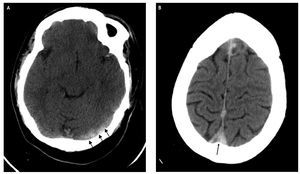

Figura 1 Tomografia computada cranial sense contrast iodat. A. augment de la densitat al si transvers esquerre (fletxes) amb mala definició de les vores, indicatiu de trombe recent. B. Nivell superior. Augment de la densitat al si longitudinal superior (fletxa).

Home de 27 anys amb SD, que va acudir al servei d'urgències de l'hospital per cefalea, vòmits i hemiparèsia esquerra. A l'exploració física era conscient, orientat, collaborador, i tenia una pressió arterial de 150/75 mmHg, una freqüència cardíaca de 68 ppm i no presentava febre. Mostrava una auscultació cardiopulmonar normal. A l'exploració neurològica va destacar una endotropia de l'ull dret en posició basal de la mirada, hemiparèsia esquerra: MSI proximal 0/5, distal 4-/5, MII proximal 3/5, distal 2/5, ROT conservats. En l'analítica que va fer a urgències no es van observar alteracions significatives en l'hemograma ni en la bioquímica. L'estudi de coagulació no es va poder obtenir perquè era una mostra insuficient. Van sol·licitar-hi una tomografia computada (TC) cranial urgent en què es van observar signes indirectes de TVC consistents a una hiperdensitat del si longitudinal superior i el si transvers esquerre, i èctasi i hiperatenuació d'algunes venes corticals (fig. 1). La ressonància magnètica (RM) cranial va confirmar els descobriments de la TC (fig. 2). La causa d'aquesta extensa trombosi encara no està clara. Es va iniciar un tractament anticoagulant amb heparina i, a continuació, es va administrar Sintrom® durant 1 mes, amb la qual cosa hi va haver una evolució clínica favorable i actualment no presenta símptomes.